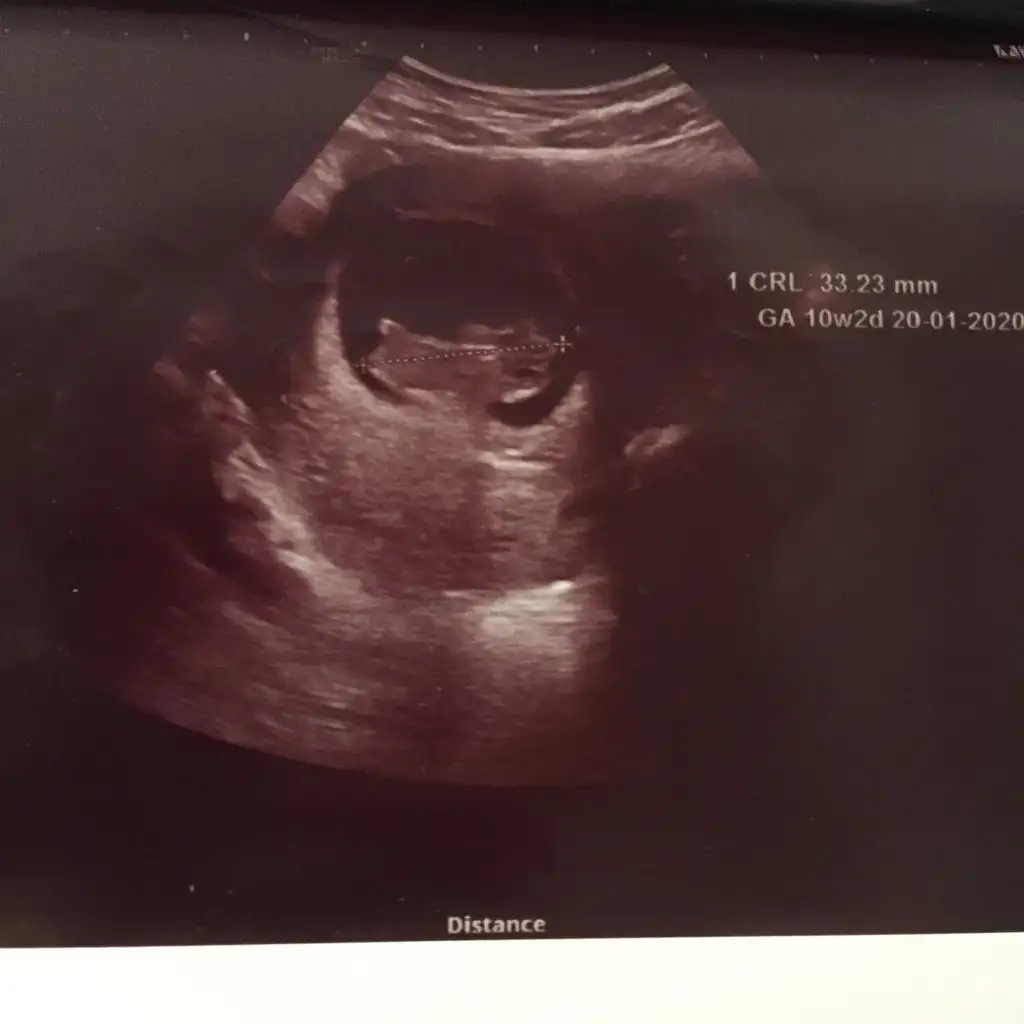

merhaba 12+0 acaba yorumlayabilir misiniz ben cıkintı gormedim

Eklentiler

• 20190722_143243.webp

20190722_143243.webp

19,9 KB · Görüntüleme: 83